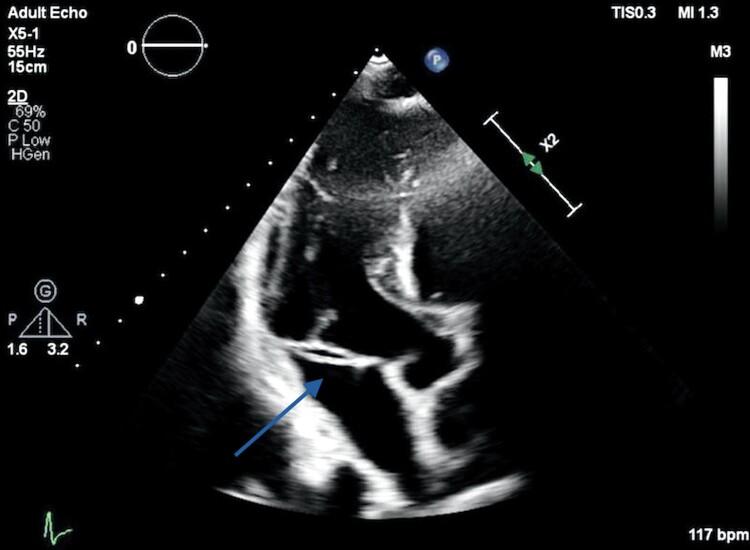

A 59-year-old man with a history of metastatic duodenal carcinoma was admitted with a 2-week history of fever and rigors. Inflammatory markers were elevated and blood cultures positive for . Transoesophageal echocardiography performed to investigate for infective endocarditis revealed a 2.3 cm long, thin fibrous band attached to the posterior mitral annulus and extending to the base of the middle scallop of the anterior mitral valve leaflet causing localized tethering, but no valve dysfunction. The band was felt to represent a bystander anatomic variant unrelated to the sepsis, which was most likely gastrointestinal in origin. The patient responded well to intravenous antibiotics.

一名有转移性十二指肠癌病史的59岁男性因发热和寒战2周入院。炎症指标升高,血培养阳性。为调查感染性心内膜炎而进行的经食管超声心动图检查显示,一条2.3厘米长的细纤维带附着于二尖瓣后环,并延伸至二尖瓣前叶中间扇贝形瓣叶的基部,导致局部受限,但无瓣膜功能障碍。该纤维带被认为是一种与脓毒症无关的旁观者解剖变异,脓毒症很可能起源于胃肠道。患者对静脉使用抗生素反应良好。

The presence of an abnormal intracardiac structure in the setting of occult infection should always raise the suspicion of infective endocarditis. Using detailed 2D multiplanar and 3D transoesophageal echocardiography, we were able to identify the anomalous band and exclude any overt infective vegetations attached to the band or the leaflets. Once identified, treatment options range from conservative management to surgical resection and mitral valve surgery if concomitant valvular dysfunction is demonstrated.

结论

在隐匿性感染情况下出现心脏内异常结构应始终怀疑感染性心内膜炎。通过详细的二维多平面和三维经食管超声心动图,我们能够识别出异常纤维带,并排除附着于该纤维带或瓣叶上的任何明显感染性赘生物。一旦识别出来,治疗方案从保守治疗到手术切除,如果证明伴有瓣膜功能障碍则进行二尖瓣手术。